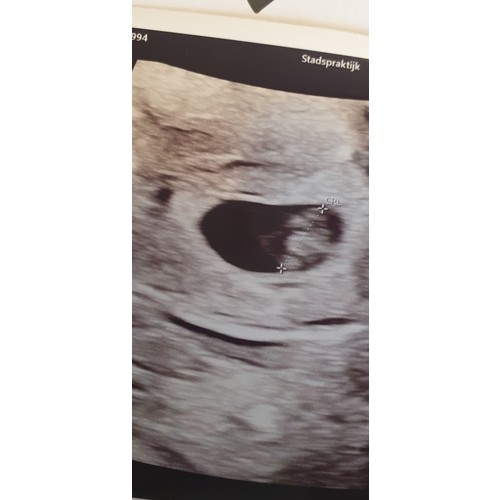

Bij mij is de echo uitwendig gemaakt. Was toen precies 8 weken. Zoals ik he ...

Dit is dan het model voor een uitwendige echo ! Inwendig is het andersom

Oke dan ben ik heel erg benieuwd wat dit dan eventueel kan zijn volgens de ramzi methode dit is een inwendige echo geweest bij 8 weken zwangerschap